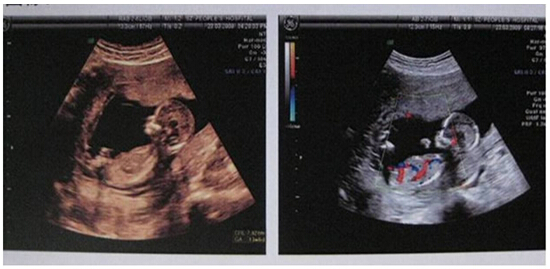

应用柯尼卡美能达彩色多功能复合机打印的彩超报告图像清晰、色彩真实